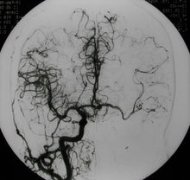

頸動脈海綿竇瘺(carotid-cavernous fistula,CCF)一般指頸內(nèi)動脈海綿竇段的動脈壁或其分支發(fā)生破裂,以致與海綿竇之間形成異常的動靜脈交通。由頸內(nèi)動脈和(或)頸外動脈的硬腦膜支血管與海綿竇形成側(cè)異常交通稱為海綿竇硬膜動靜脈瘺。 頸動脈海綿竇瘺...[詳細(xì)]

頸動脈海綿竇瘺是指海綿竇段的頸內(nèi)動脈本身或其在海綿竇內(nèi)的分支破裂,與海綿竇之間形成異常的動靜脈溝通,少數(shù)頸動脈海綿竇瘺由頸外動脈供血,特稱頸外動脈海綿竇瘺。75%以上的為外傷引起,稱為外傷性CCF,其余無外傷史者,稱為自發(fā)性海綿竇瘺。最常見...[詳細(xì)]

頸動脈海綿竇瘺(carotid-cavernous fistula,CCF)一般指頸內(nèi)動脈海綿竇段的動脈壁或其分支發(fā)生破裂,以致與海綿竇之間形成異常的動靜脈交通。由頸內(nèi)動脈和(或)頸外動脈的硬腦膜支血管與海綿竇形成側(cè)異常交通稱為海綿竇硬膜動靜脈瘺。 (一)發(fā)病原因...[詳細(xì)]